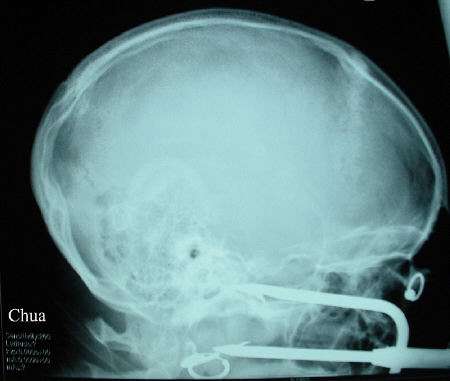

This teenager was harpooned

during a dispute. One of the prongs entered the lower orbit resulting in

globe perforation. CT scan showed the prongs narrowly missed the brain.

The harpoon was removed in conjunction with the maxillary facial surgeon.

The globe underwent primary repair at the same time.